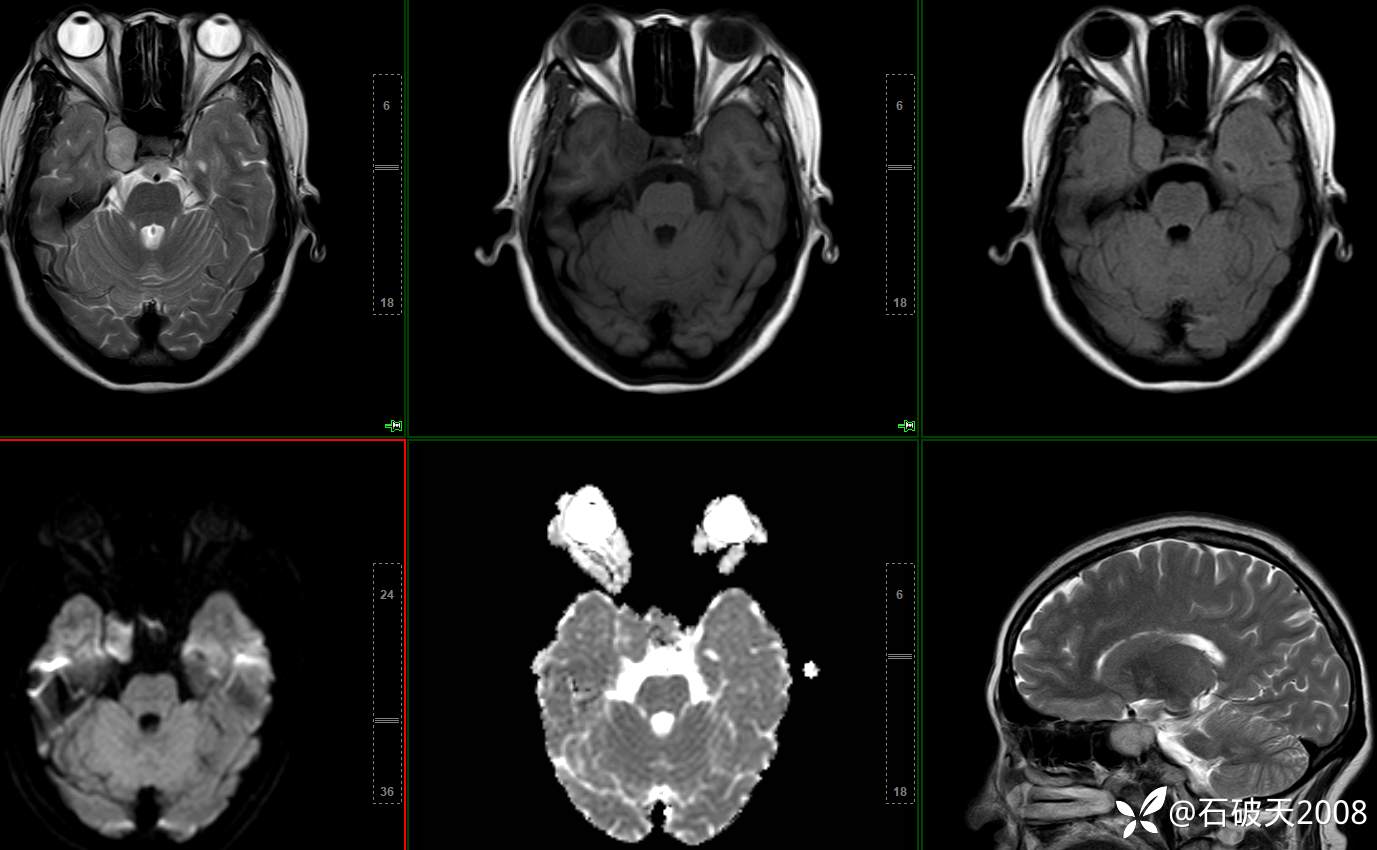

鞍旁占位,相信讨论区会有两种判断(病理已公布)

胡志勇HZY 达人已点赞女 48岁 主 诉:头晕、右眼复视1月余。

现病史:患者1月前无明显诱因出头晕、右眼视物复视、重影;向右侧视物时明显,余方向及左眼视物无特殊不适,头晕为非旋转性,不伴随体位变化;无恶心、呕吐、胸闷、肢体言语活动不利症状;为行系统治疗来院门诊“颅内占位性病变”收住院。发病来患者神志清,精神差,饮食睡眠可,大小便正常,体重无下降。

平扫